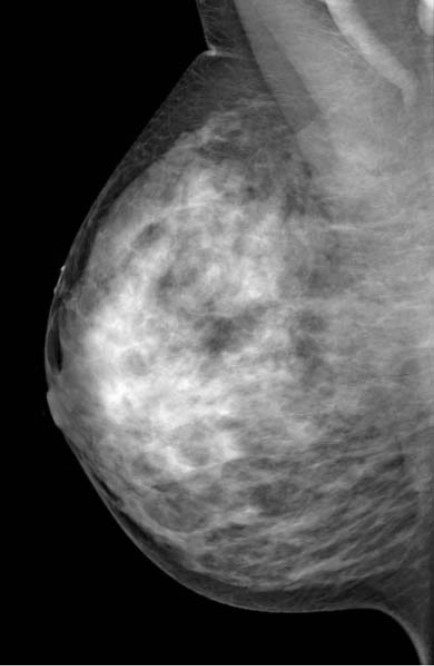

◂Breast Anatomy